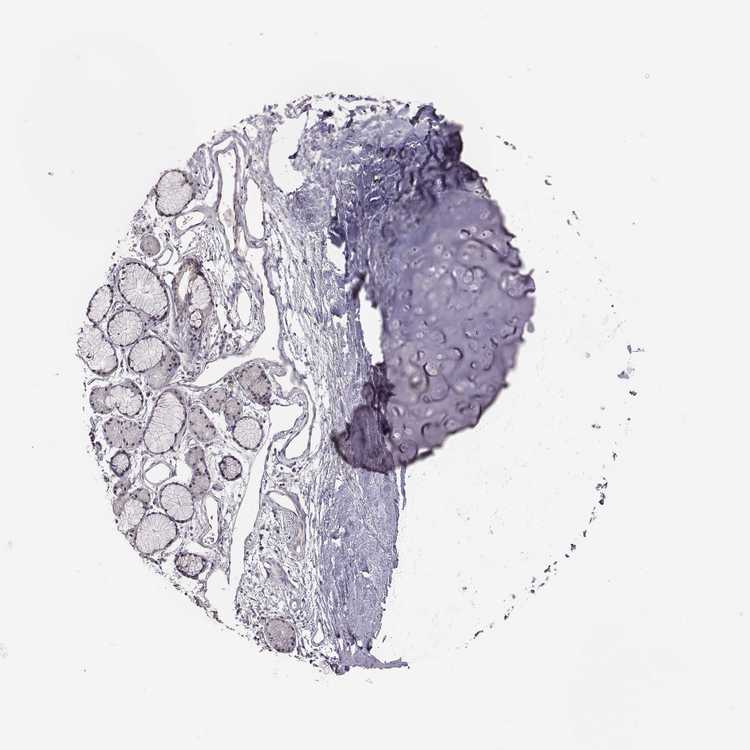

SOFT TISSUE 1 - Antibody stainingi

Antibody staining in the annotated cell types in the current human tissue is reported as not detected, low, medium, or high, based on conventional immunohistochemistry profiling in selected tissues. This score is based on the combination of the staining intensity and fraction of stained cells.

Each image is clickable and will lead to virtual microscopy that enables deeper exploration of all samples and also displays staining intensity scores, fraction scores and subcellular localization as well as patient and tissue information for each sample.

Antibody HPA071508

Chondrocytes Not detected

Fibroblasts Not detected

SOFT TISSUE 2 - Antibody stainingi

Peripheral nerve Not detected